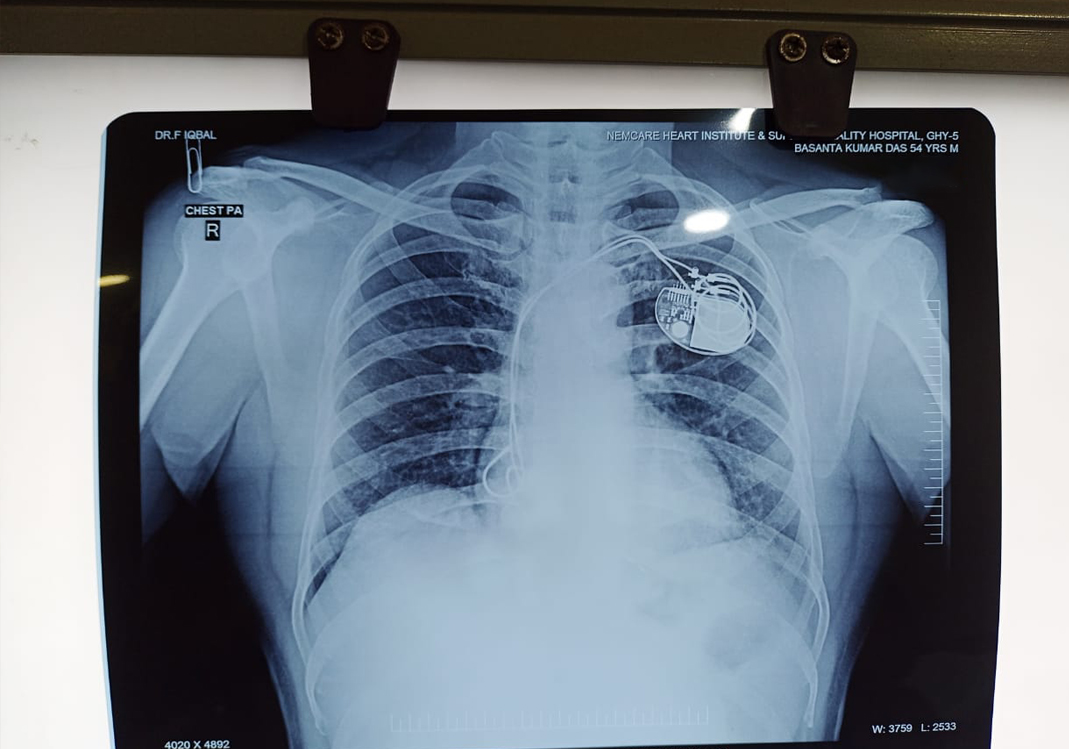

Basanta Kumar Das

My father, a loving and hardworking man, has always been the pillar of our family — full of life, laughter, and strength. But recently, he suffered not just one, but two heart attacks, leaving his heart critically weak. Doctors had to urgently implant a pacemaker to save his life.

We thought he was on the path to recovery… But soon after, things took a painful turn. The pacemaker’s lead failed. A second emergency operation was performed, but sadly, it didn’t succeed.

Now, he needs a third, life-saving heart operation — and it must happen soon.